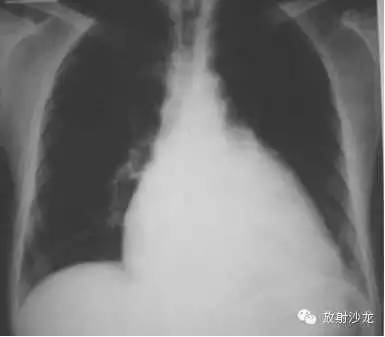

X线表现为心脏增大,肺淤血,间实质肺水肿,胸腔积液

左房右室增大